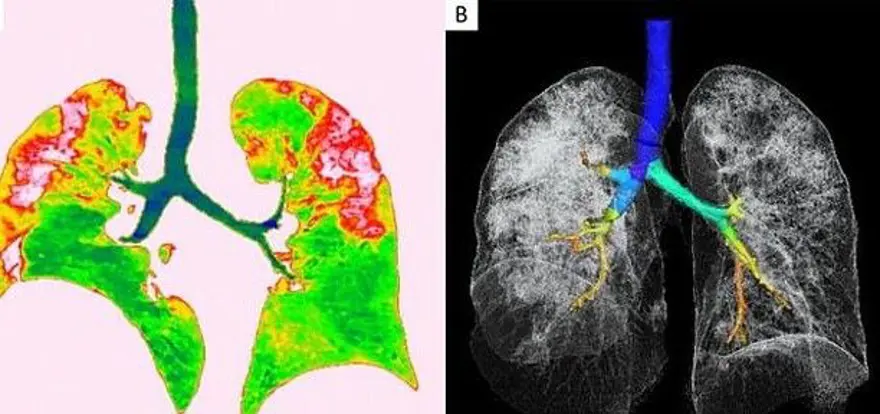

Solda yer alan fotoğrafta kırmızı olarak görülen alanlarda nodüller, sağ tarafta ise akciğer ve trakeanın üç boyutlu görüntüsü yer alıyor. Beyaz alanlarda corona virüsün tahribi görülüyor.